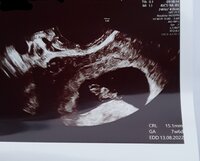

Toisaalta päätökseen vaikutti myös se, että kohtuullisen matkan päässä Lahdessa oli Perhe-Artella kätilön tekemä ultra 79e, mikä kummasti madalsi kynnystä...

meillä onneksi neuvolassa on ultra, niin pääsi siellä tarkistamaan tilanteen.